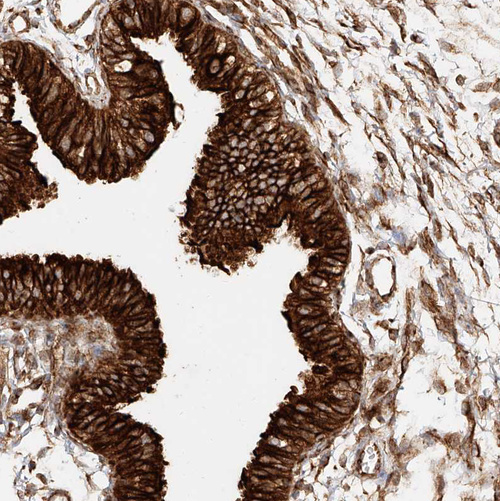

Immunohistochemical staining of human tonsil shows strong cytoplasmic positivity in germinal center cells.